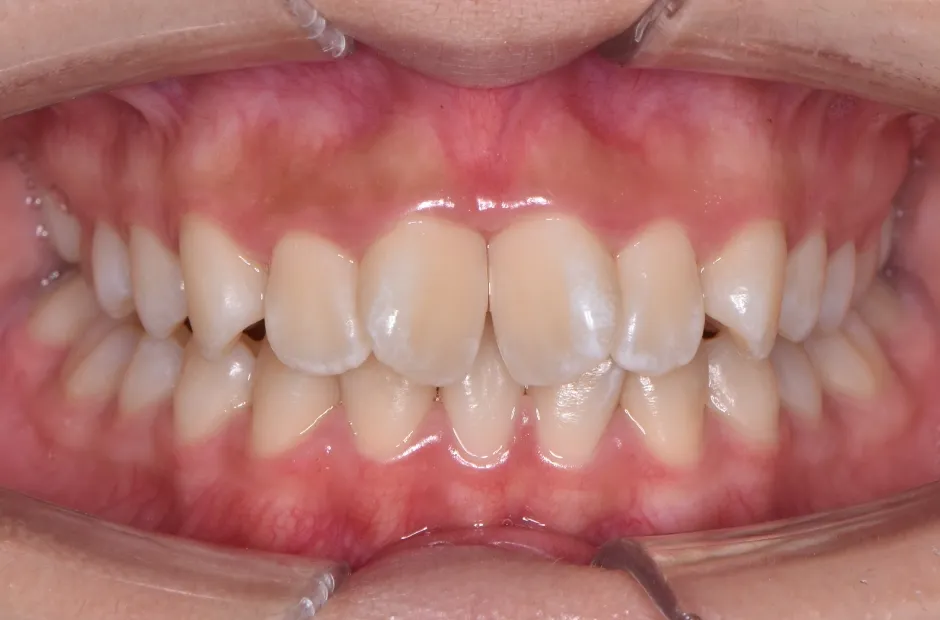

治療症例

ブラケット矯正

前歯部反対咬合

| 診断名・主訴 | 前歯部反対咬合 |

|---|---|

| 年齢・性別 | 14歳・男性 |

| 治療期間・回数 | 1年2か月 |

| 治療に用いた主な装置 | ブラケット矯正 |

| 抜歯部位 | なし |

| 治療費 | 60万円(税抜) |

| リスク・副作用 | 装置による違和感・疼痛・歯肉退縮・歯根吸収・虫歯のリスクなど |

治療前

治療後